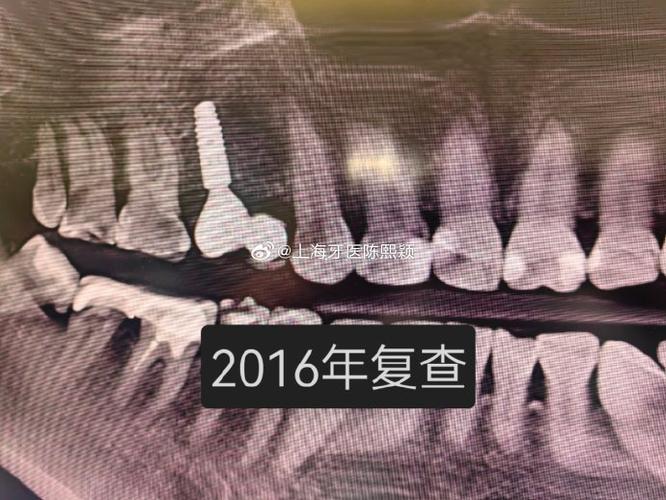

- 临床实践: 在80年代末至90年代初,九院就已经开始为符合条件的患者实施种植牙手术,并积累了宝贵的早期临床经验,这被认为是上海地区最早、最系统、最持续开展种植牙临床实践的机构。

- 系统开展与专科建立: 上海第九人民医院口腔种植科的建立和发展,标志着种植牙技术在上海从零星尝试走向系统化、专科化、规范化,该科室在90年代中后期就已经是国内种植牙领域的标杆,培养了大批人才,制定了行业标准,并持续推动技术进步,说九院是上海种植牙技术的摇篮和发源地是业界公认的。